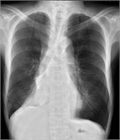

1. 無気肺とは肺組織が虚脱し、肺の含気が低下した状態である。

1. 閉塞性無気肺(腫瘍、粘液栓、異物、気管支結核など)と非閉塞性無気肺(炎症などによる肺実質の虚脱、受動性無気肺、円形無気肺など)に大別される。

1. 胸部X線撮影で無気肺が疑われたら、まずは胸部造影CTで鑑別をすすめ、必要に応じ喀痰培養、喀痰細胞診、気管支鏡などを行う。